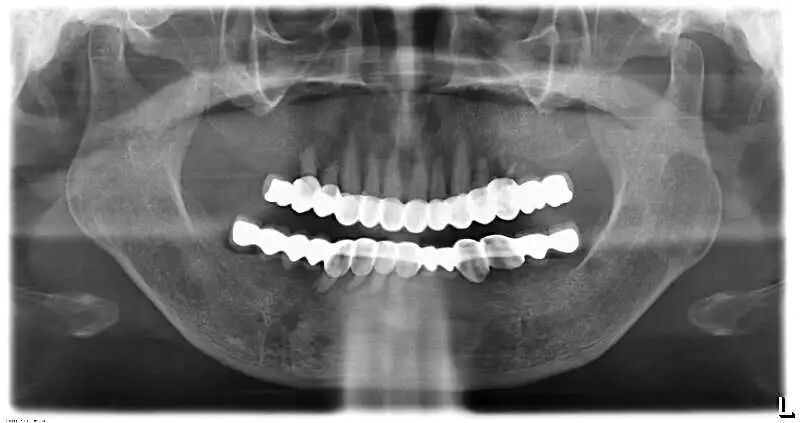

接下来再谈谈另一种不太与时俱进的烤瓷修复方式,即四环素牙和某些牙色不佳患者的全口烤瓷美容,同样的道理,十几年前因技术局限而造成相当部分患者被磨小了全口牙齿戴了烤瓷牙,以牺牲牙质的代价换取了阶段性的美观,后期乃至一辈子都在为不断出现的并发症而伤透脑筋。我们可以百度一下“明星做烤瓷牙”,百度虽说在涉及医疗的资讯上很不靠谱,但涉及明星的个人颜值信息搜索上却是相当全面。

全口牙磨小后是个什么状态,烤瓷以后又是什么效果,因人而异,但无论美观上做得多好,长期隐患如同不定时炸弹,多磨一颗牙就多一分风险。

这种全口烤瓷,以前的病例非常多,无论是公立医院还是私人诊所。但今天,微创的瓷贴面技术逐渐成熟,在理念上渐渐取代了烤瓷,可以达到磨牙量少(部分甚至完全不磨牙),对牙髓保护佳,美观自然的修复效果。